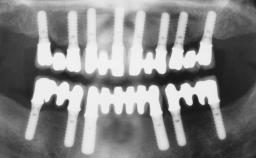

Conventional Loading of Eight Implants in the Maxilla and Final Restoration with a Full-Arch Gold-Ceramic FDP

A 35-year-old Caucasian female presenting with advanced periodontal disease involving both the maxillary and the mandibular dentition was referred for evaluation. The patient, a non-smoker in good general health, requested treatment for recurrent periodontal abscesses, tooth mobility, and discomfort during chewing, as well as restoration of her missing teeth with a fixed prosthesis to improve mastication and esthetics. All residual maxillary teeth exhibited plaque deposits, deep pockets, bleeding on probing, and class III mobility and were evaluated as hopeless. All residual mandibular teeth except tooth 37 could be maintained after periodontal therapy.

# of Implants 8

Type of Implants One-Piece

Defining Characteristics Fully edentulous upper jaw to be rehabilitated with four or more implants

Defining Characteristics Fully edentulous upper jaw to be rehabilitated with an implant-borne fixed dental prosthesis